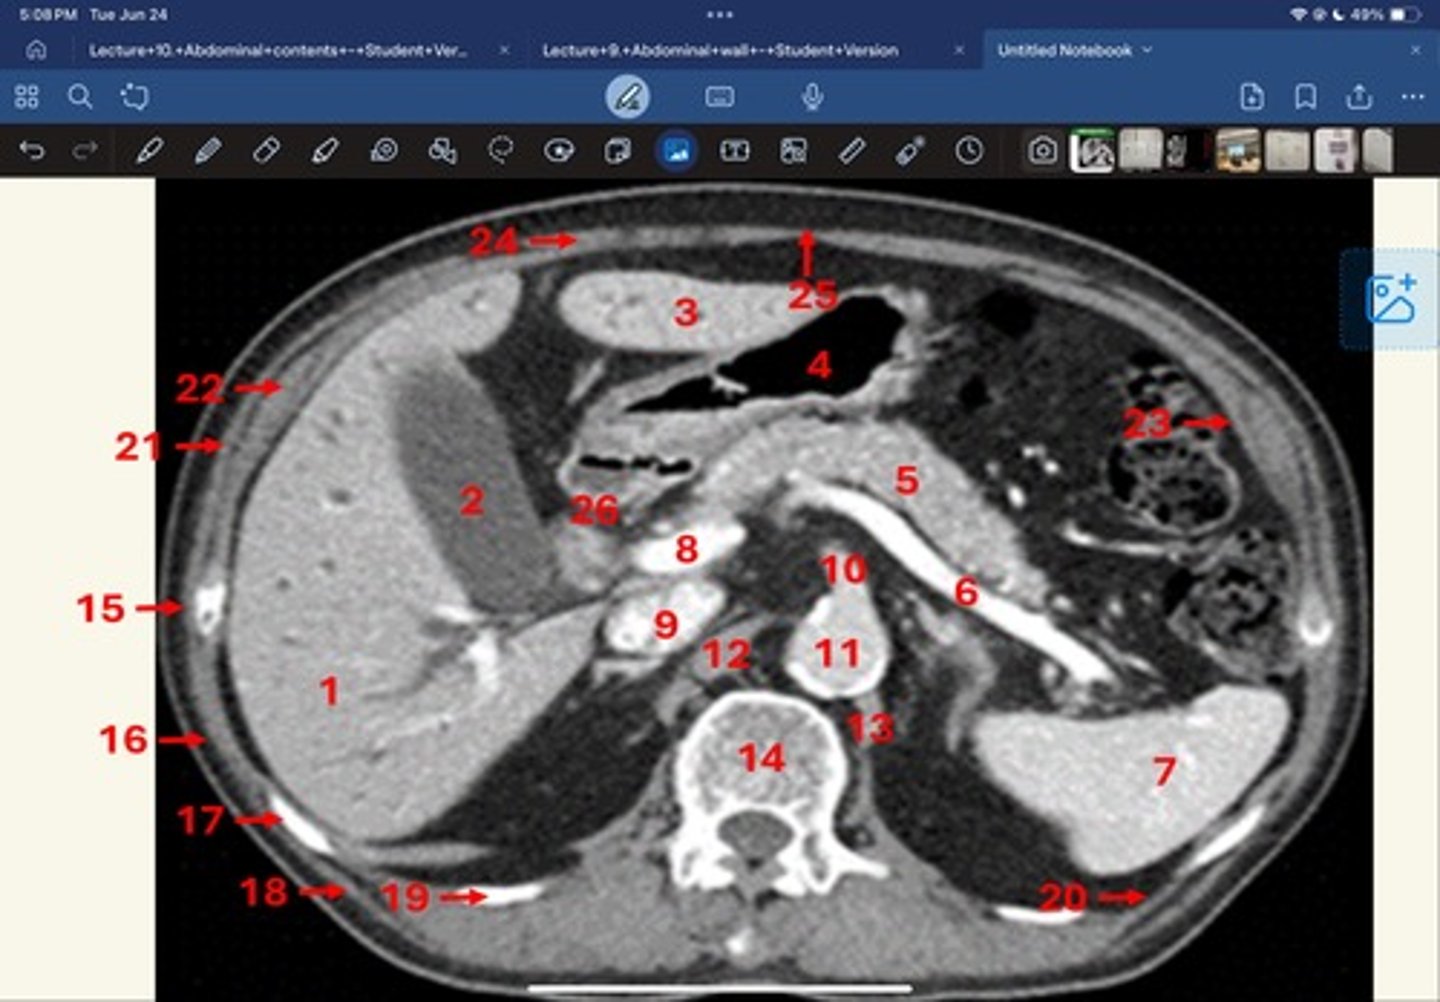

Right lobe of liver

What is 1

Gallbladder

What is 2

Left lobe of liver

What is 3

Stomach, pylorus

What is 4

Pancreas

What's 5

Splenic vein

What's 6

Spleen

What's 7

superior mesenteric vein

What's 8

Inferior vena cava

What's 9